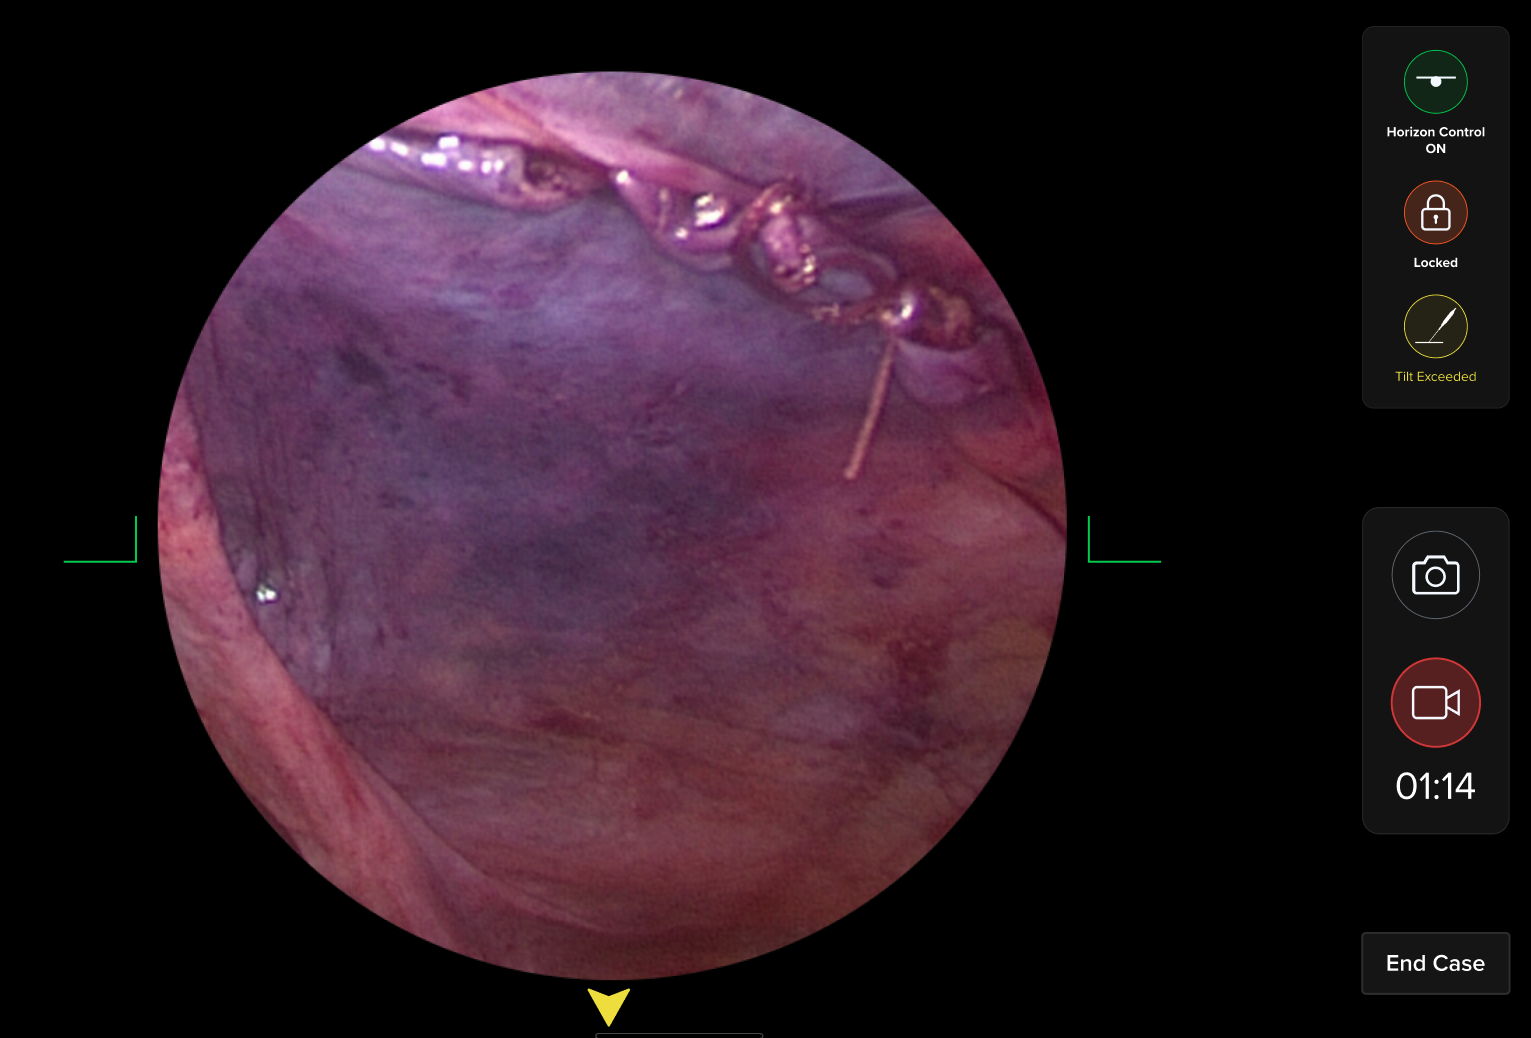

HUD Design: Surgery-Ready Interfaces

Operating rooms aren't like offices. I designed interfaces specifically for heads-up displays, considering lighting, distance, and the critical nature of surgical procedures.

- Created HUD displays that surgeons could actually use